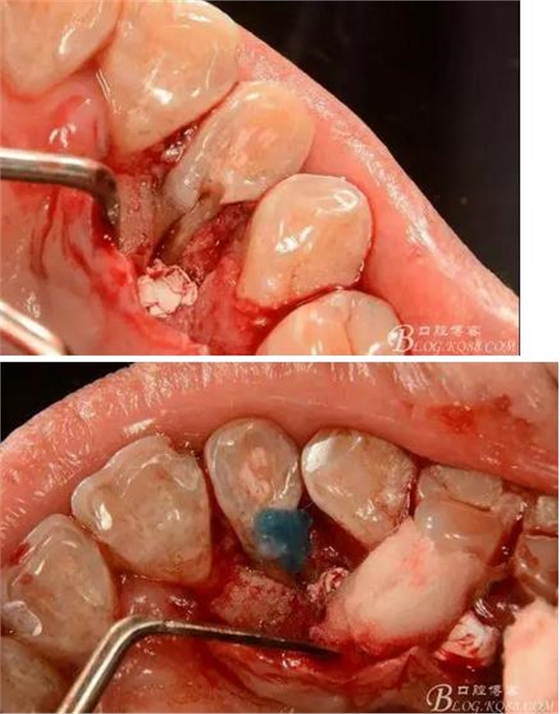

(3)處理:常規(guī)開髓,修整髓腔,15#k銼探查根管,根管測(cè)量?jī)x確定工作長度,根長22mm,大錐度手動(dòng)銼完成根管預(yù)備,沒換一次銼沖洗根管一次,消毒,干燥根管,暫封維他派克斯。4%阿替卡因腎上腺素行11至14局部浸潤麻醉、消毒、鋪巾,做11-14腭側(cè)牙齦水平切口并翻瓣暴露12腭側(cè)骨缺損區(qū),清理肉芽組織及壞死骨組織,清潔術(shù)區(qū),磨除根面溝,制備固位溝槽,酸蝕,粘接,光固化樹脂修復(fù)根面缺損區(qū),阻斷牙周感染途徑。拋光樹脂,沖洗創(chuàng)面,復(fù)位齦瓣,局部敷料壓迫一分鐘,對(duì)位縫合齦瓣。術(shù)后抗炎治療,7d線。

(4)隨訪:術(shù)后患者無明顯疼痛不適癥狀。

(6)復(fù)診:原暫封材料再位,牙周無明顯異常與不適,常規(guī)清潔根管,H銼清除根管內(nèi)維他,次氯酸鈉終末消毒,干燥根管,單尖測(cè)壓發(fā)充填根管,術(shù)后拍片到位。